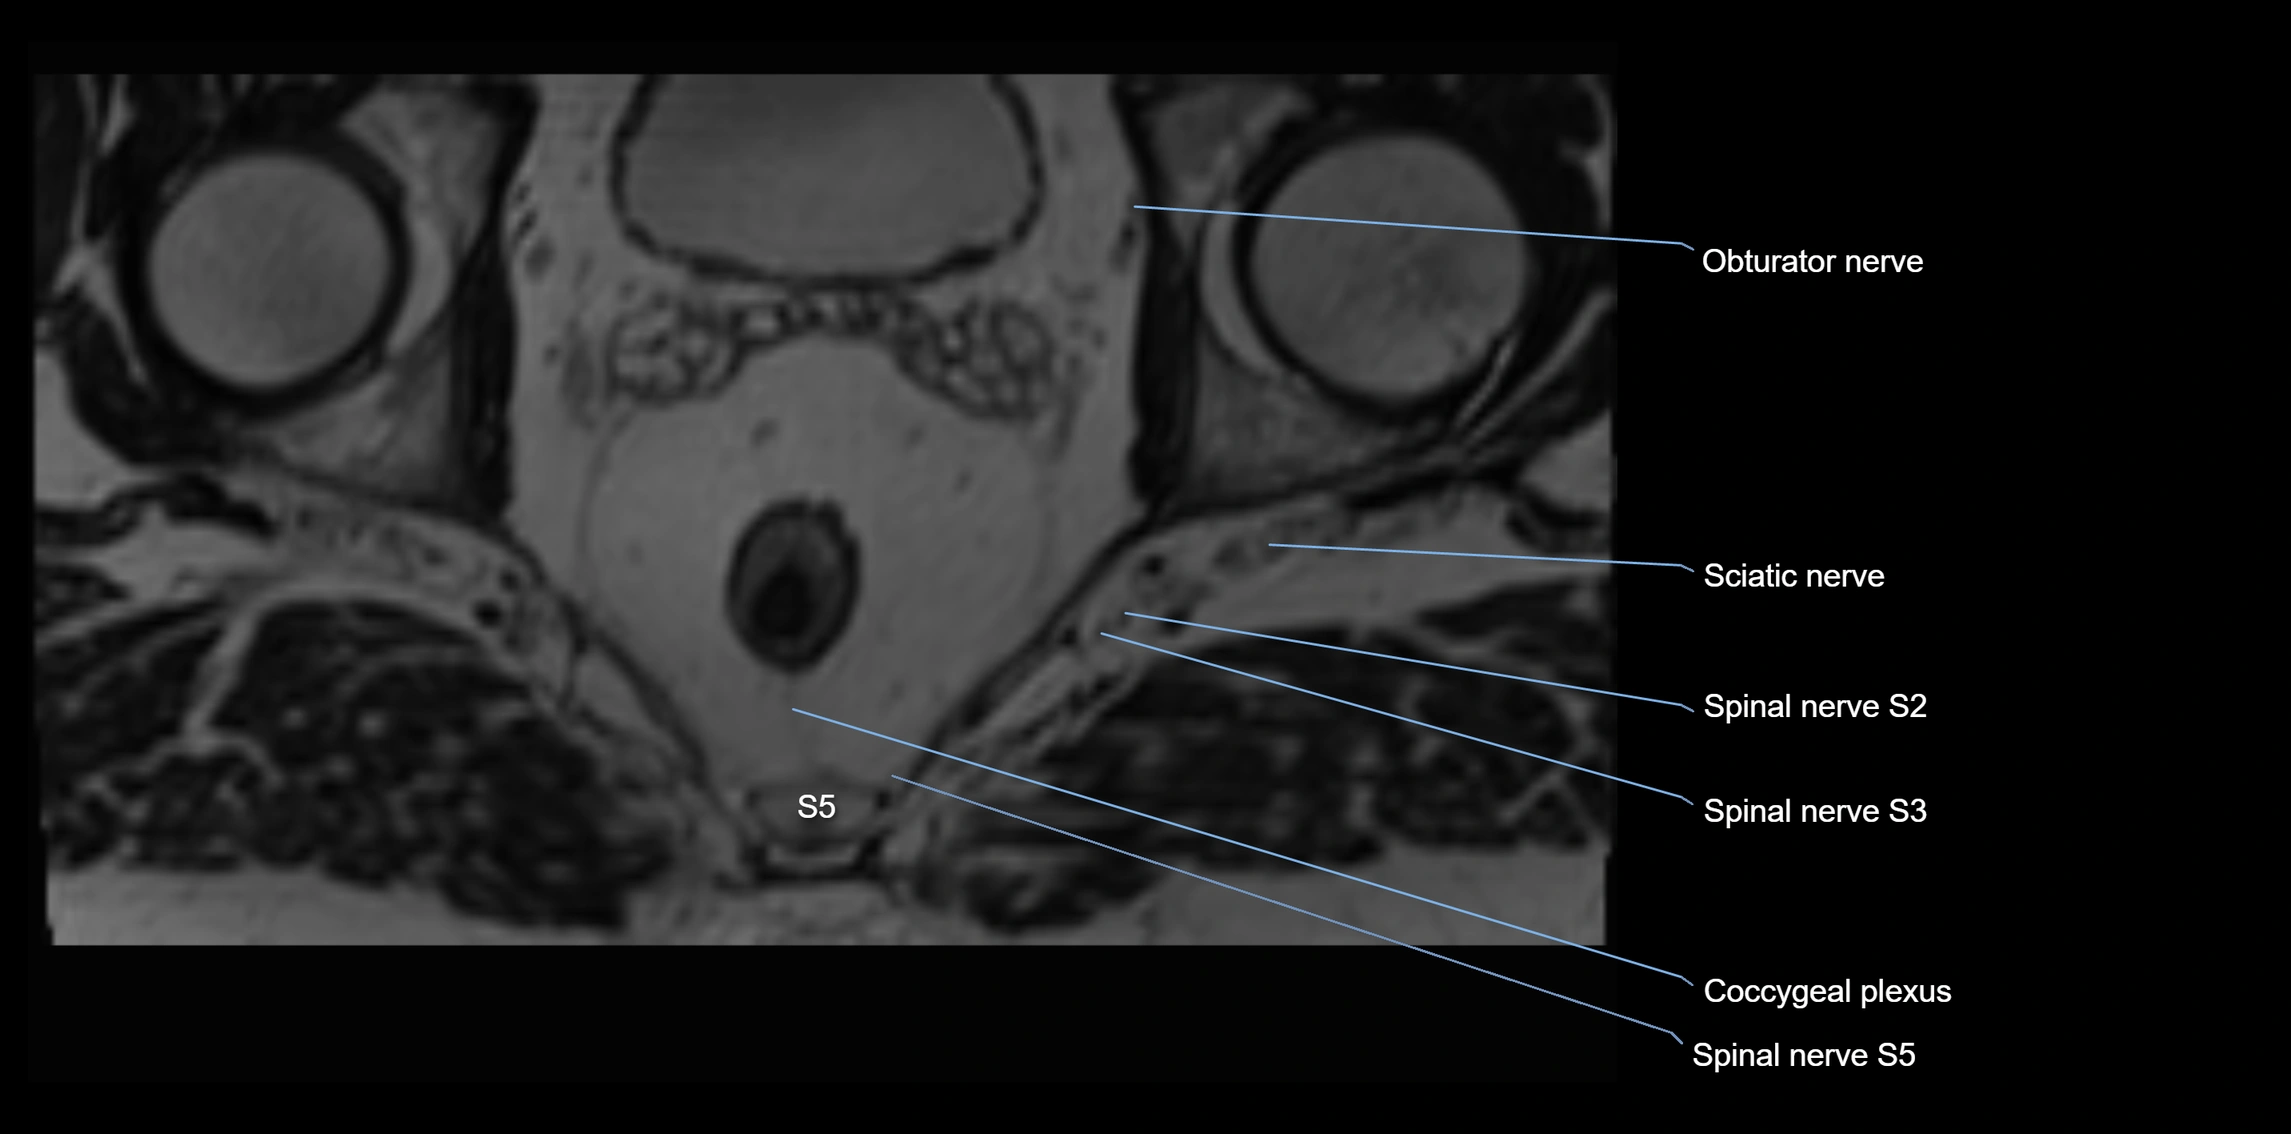

The anococcygeal nerve is a small sensory nerve derived from the coccygeal plexus, which itself is formed by the ventral rami of S4, S5, and the coccygeal nerve (Co1). Although tiny, this nerve plays an important role in supplying the skin of the coccyx and the area between the anus and coccyx. It passes through the sacrotuberous ligament and runs in the midline behind the coccyx.

Despite its small size, the anococcygeal nerve is clinically important because of its involvement in coccygodynia (coccyx pain) and perineal pain syndromes.

MRI image

image